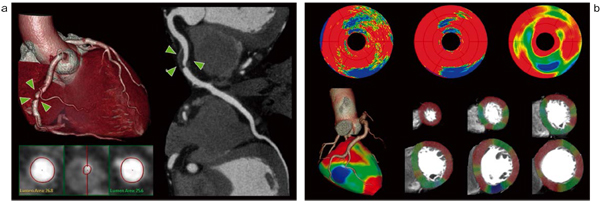

冠動脈疾患において心筋に虚血や梗塞がある場合,正常心筋に比べ,同部位は低灌流域として描出されることが広く知られている2)。“Myocardial DefectAssessment(MDA)”は,弊社ネットワーク型ワーステーションである「IntelliSpace Portal(ISP)」で使用可能な心筋低灌流域検出支援アプリケーションである。

MDA は,AHA セグメント分類に基づき,心筋のCT 値と解析アルゴリズム3)に従い,各セグメントの心筋低灌流域を自動抽出~解析し,3種類の定量結果として出力する(図3)。MDAの解析に必要なデータは,原則として拡張期のシンスライスデータのみであるため,昨今多くの施設で行われているprospectively gated axial スキャンのデータから,冠動脈の形態情報に心筋の機能情報を付加することができる。加えてMDAは,弊社心臓解析アプリケーション“Comprehensive CardiacAnalysis”のアドオン機能として動作するため,解析者は冠動脈から心筋性状,さらには心機能までの一連の解析を短時間で包括的に行うことが可能である。

図3 Myocardial Defect Assessmentの解析画面

a: 右冠動脈高度狭窄症例のCT 像

左:VR 像と血管短軸像 右:CPR 像

b: MDA による画像解析結果

上段左:HU map。心筋全体のCT 値から特定の閾値を利用 上段中:Defect probability map。

低灌流域が統計学的にどこにどの程度分布するかを推定

上段右:(Endo-Epi)map。心筋の内膜側と外膜側のCT 値の差分を算出

下段:(Endo-Epi)mapと冠動脈VRツリーのフュージョン像。

右冠動脈高度狭窄に一致した支配領域(下壁)に低灌流域が確認できる。